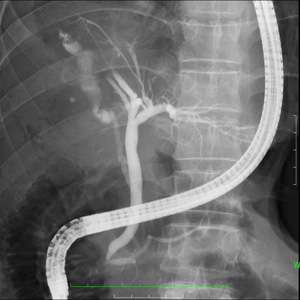

- 内視鏡的胆道膵管造影検査(胆道、膵管の検査) 胃カメラを使って、膵管や胆道を観察する検査で、胆管に石がある場合はその石を砕いて治療も行っています。

Q3) ERCP検査と胃カメラ検査と何が違うのですか?

![]() |

A3) どちらの検査も内視鏡を挿入する検査ですが、胃カメラは胃の壁を観察して病変を見つける検査で、ERCPは内視鏡の側溝から細い管を使って、胆管や膵管を造影して観察する検査です。 |